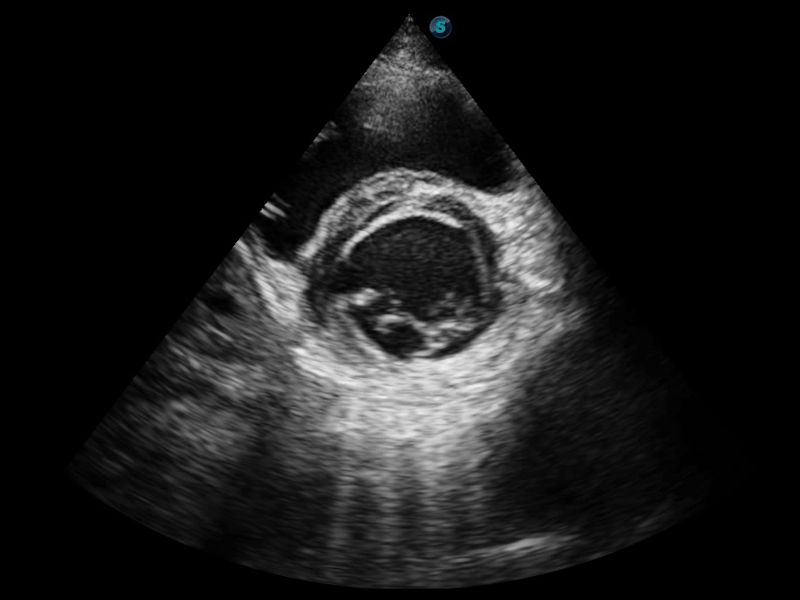

狗万官方网站通过不断的技术创新,为大众的生命健康提供持续关爱。P12 Plus采用全新一代超声成像平台,新平台旨在将真实还原组织解剖结构作为首要目标。平台采用全新集成化硬件模块,搭载新一代芯片,系统性能得到大幅提升,为您的诊断提供了丰富的临床信息。优异的图像表现,丰富的探头配置,全面的应用功能,为您日常诊断提供了可靠的助手。

凭借狗万官方网站先进的成像技术和优异的探头技术提供的清晰的图像表现,您可以更自信地做出临床决策。